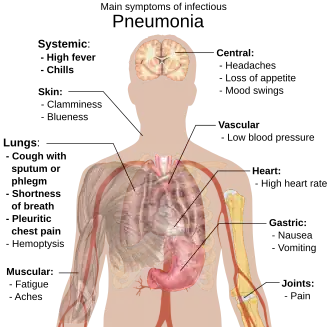

Signs and symptoms

People with infectious pneumonia often have a productive cough, fever accompanied by shaking chills, shortness of breath, sharp or stabbing chest pain during deep breaths, and an increased rate of breathing.[9] In elderly people, confusion may be the most prominent sign.[9]

The typical signs and symptoms in children under five are fever, cough, and fast or difficult breathing.[23] Fever is not very specific, as it occurs in many other common illnesses and may be absent in those with severe disease, malnutrition or in the elderly. In addition, a cough is frequently absent in children less than 2 months old.[23] More severe signs and symptoms in children may include blue-tinged skin, unwillingness to drink, convulsions, ongoing vomiting, extremes of temperature, or a decreased level of consciousness.[23][24]

Bacterial and viral cases of pneumonia usually result in similar symptoms.[25] Some causes are associated with classic, but non-specific, clinical characteristics. Pneumonia caused by Legionella may occur with abdominal pain, diarrhea, or confusion.[26] Pneumonia caused by Streptococcus pneumoniae is associated with rusty colored sputum.[27] Pneumonia caused by Klebsiella may have bloody sputum often described as "currant jelly".[28] Bloody sputum (known as hemoptysis) may also occur with tuberculosis, Gram-negative pneumonia, lung abscesses and more commonly acute bronchitis.[24] Pneumonia caused by Mycoplasma pneumoniae may occur in association with swelling of the lymph nodes in the neck, joint pain, or a middle ear infection.[24] Viral pneumonia presents more commonly with wheezing than bacterial pneumonia.[25] Pneumonia was historically divided into "typical" and "atypical" based on the belief that the presentation predicted the underlying cause.[29] However, evidence has not supported this distinction, therefore it is no longer emphasized.[29]